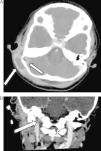

Caso 2: niña de 3 años sin antecedentes de interés, que presenta fiebre y otalgia de 14 días de evolución. Recibe en este tiempo tratamiento con cefixima y amoxicilina oral sin mejoría. En las 48h previas al ingreso inicia tortícolis, otorrea derecha y masa fluctuante retroauricular. En la analítica destacan 11.950/μl neutrófilos y PCR 117,9mg/L. En la TC craneocervical se observa mastoiditis aguda derecha complicada con absceso subperióstico y tromboflebitis del seno sigmoideo y de VYI (fig. 1A y B). Se realiza mastoidectomía y drenaje del absceso en las primeras 24h, donde se aísla Fusobacterium necrophorum resistente a clindamicina. El estudio de extensión no muestra embolismos. Se administran 7 semanas de tratamiento con amoxicilina-clavulánico. A los 8 días tras la finalización del tratamiento reaparece fiebre y elevación de reactantes de fase aguda. Se realiza nueva TC craneocervical identificándose lesiones compatibles con osteomielitis del hueso temporal. Se administra cefotaxima más metronidazol intravenoso con posterior terapia secuencial oral con metronidazol hasta cumplimentar 3 meses, con buena evolución sin secuelas.